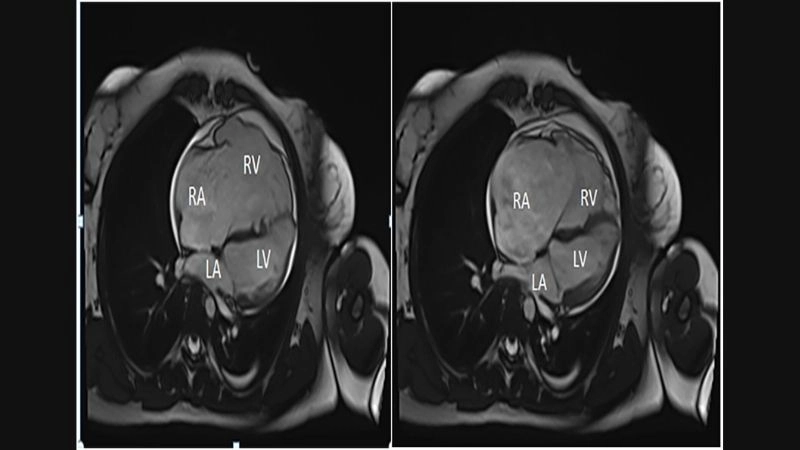

Images visual examples of Uhl's anomaly

Uhl’s anomaly is a rare congenital heart condition characterized by the near-complete absence of the right ventricular myocardium, resulting in a thin-walled and weakened heart chamber.